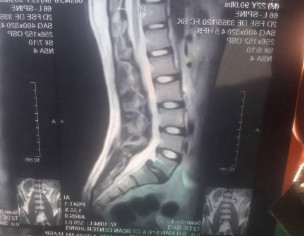

Dr. shb Aoa Muje 2019 say spondylolisthesis grade 1 hai or ab 2025 me Muje halka halka dard start hova Hai or Dono tango me dar or back pain rehta hai har time chlny phirny me mein thk hi Bth be sakta hai 30mint tak maximum Or Weight mera 59kg hai height meri 5.5 hai

Thats not grade 1 you need to be evaluated more properly